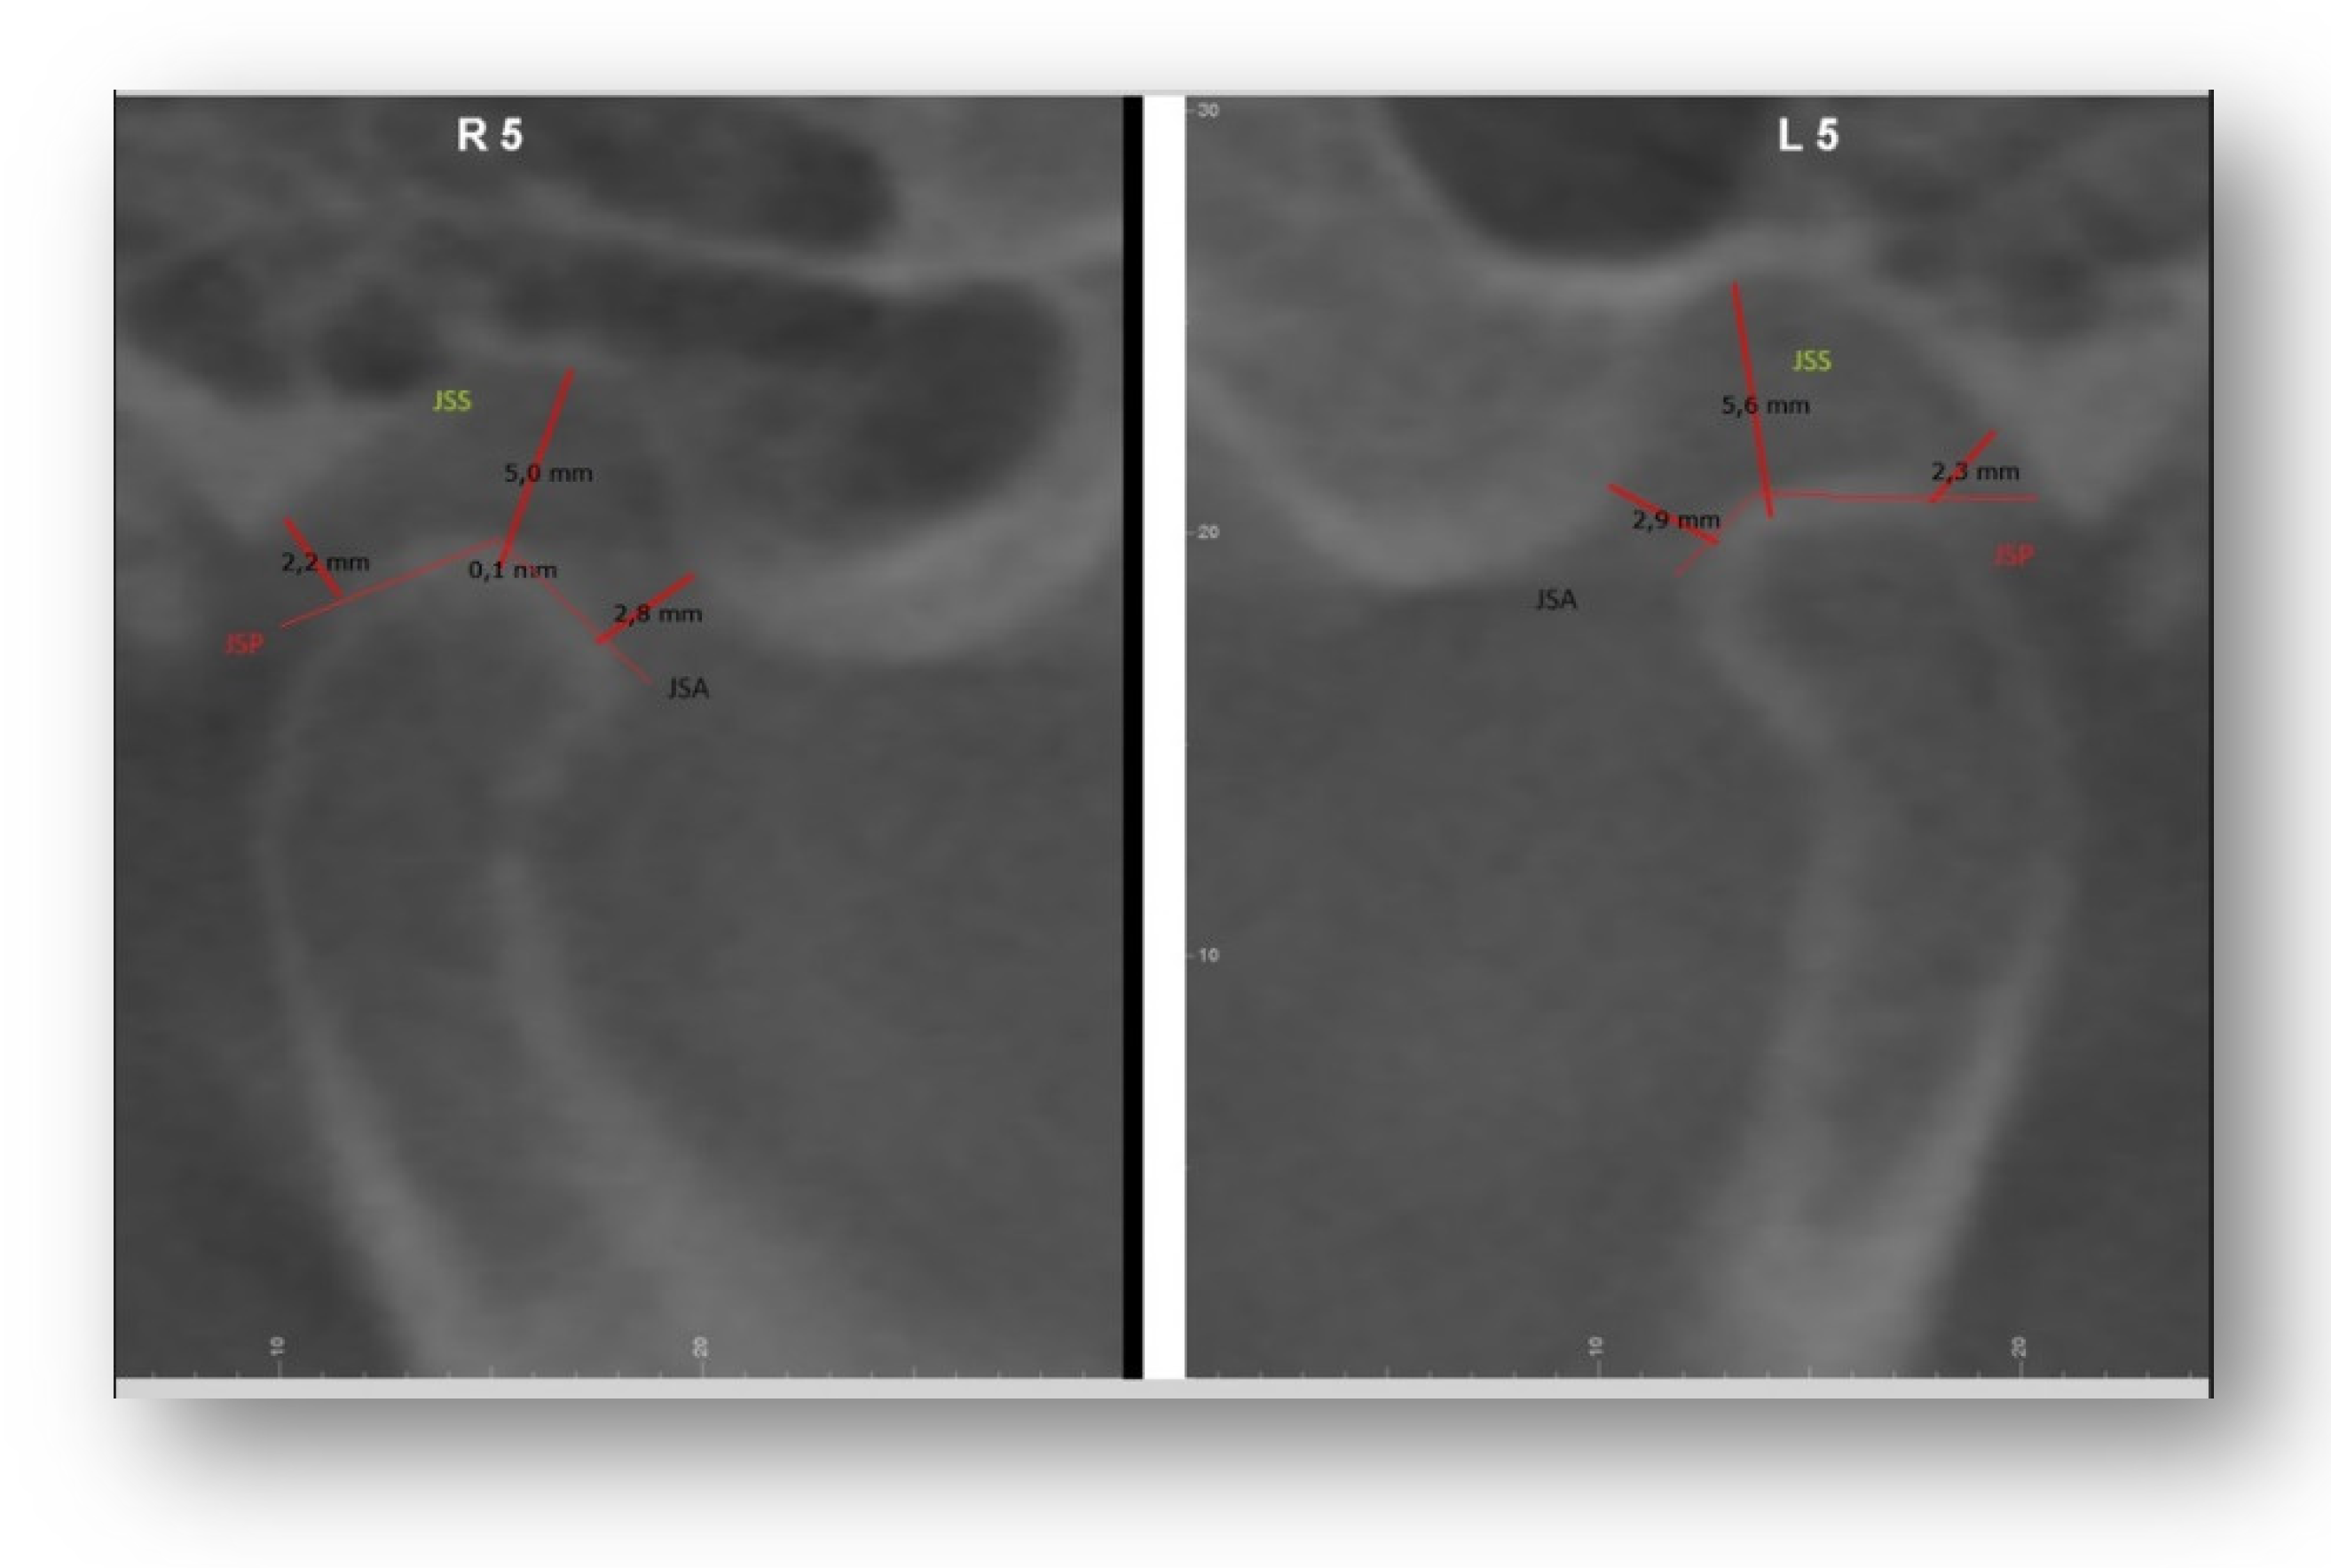

The position of the condyle was investigated through measurements made on the 2D sections obtained through the Dolphin software. All measurements of the condyle-fossa relationships were performed on the sagittal section passing through the midpoint of the distance between the medial and lateral poles of the condylar head, and perpendicular to the coronal plane. The images were then formatted and oriented according to the coronal and sagittal planes [11].

The following were calculated: JSA (minimum anterior joint distance), SSP (minimum posterior joint distance), JSS (upper joint space). The concentricity of the condyle in the fossa was calculated using the following equation by Pullinger and Hollinder [11]

Linear Ratio (LR) = (P-A) / (P+A) x 100 [Figure 1].

Where: P – The closest posterior measurement; A – The closest anterior measurement

If LR<-12 – posterior position

If -12< LR<12 – concentric position

If LR>12 – anterior position [12]

The vertical distance between the deepest point of the fossa and the most prominent upper point of the mandibular condyle was also measured [Figure 2]

A vertical distance of 1-4 mm was considered normal.

4 mm: condyle positioned inferiorly; <1mm: condyle positioned superiorly A value of 0 mm was indicated as bone contact.